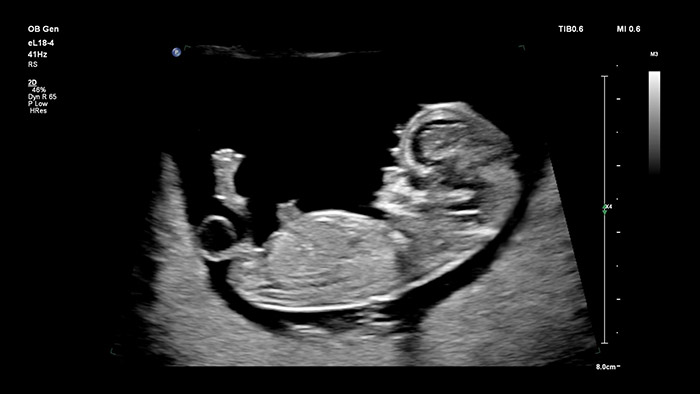

Il trasduttore Philips eL18-4 con Microflow Imaging abbatte le barriere producendo immagini 2D ad alta risoluzione e, grazie al rilevamento ultrasensibile del flusso di sangue, consente di valutare la salute fetale nel complesso durante il primo trimestre di gravidanza in cui una risoluzione ottimale e l'affidabilità diagnostica sono di importanza cruciale. Altamente versatile e progettato espressamente per applicazioni in campo ostetrico-ginecologico, il trasduttore V9-2 sfrutta la potenza della tecnologia a cristalli PureWave per acquisire immagini 2D e 3D di qualità eccezionale, pur rimanendo un sistema leggero nella propria categoria.